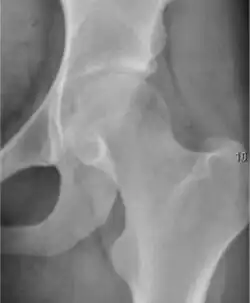

Plain radiography allows us to categorize the hip as normal or dysplastic or with impingement signs (pincer, cam, or a combination of both). Besides these, pathologic processes like osteoarthritis, inflammatory diseases, infection, or tumors can also be identified (Figure 1).[1]

Figure 1.

-

Radiography in normal hip -

X-ray in pincer impingement type of hip dysplasia -

X-ray of cam -

Hip in osteoarthritis -

Septic arthritis

There are other pathological conditions that can affect the hip joint and radiographs help to make the appropriate diagnosis. Acute bacterial septic arthritis can be diagnosed by radiographs when a fast regional osteoporosis and destructive monoarticular process develops (Figure 1(f)). In case of tuberculous or brucella arthritis it is manifested as a slow progressive process, and diagnosis may be delayed.[1]